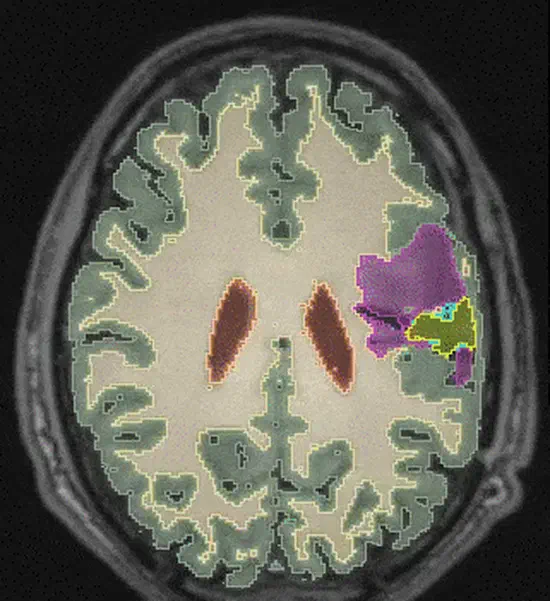

Open source PyTorch implementation of “Dorent, R., Booth, T., Li, W., Sudre, C. H., Kafiabadi, S., Cardoso, J., … & Vercauteren, T. (2020). Learning joint segmentation of tissues and brain lesions from task-specific hetero-modal domain-shifted datasets. Medical Image Analysis, 67, 101862 (📖).”